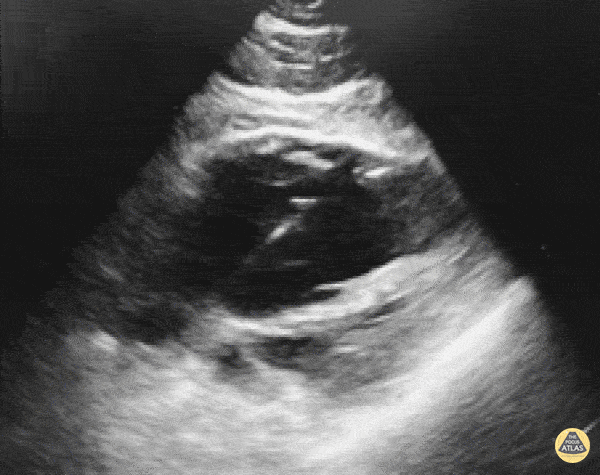

Other Cardiac Pathology - Transvenous Pacemaker Guidance

WCUME 2017 Submission for "Novel Indication" Confirming Transvenous Pacer Placement with POCUS. Dr. Sarah Medeiros, MD - Sacramento, CA